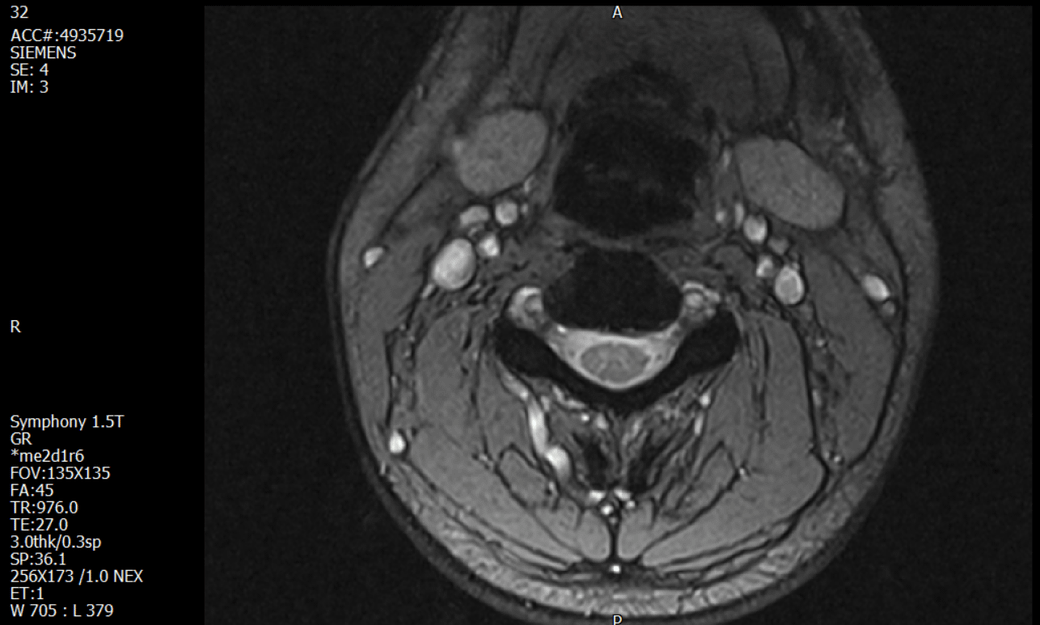

경추 요추 디스크 MRI판독 부탁드립니다.

- 3개월전 좌측 상지 저림(힘빠짐) 발생. 이틀뒤 에 좌측 하지 저림(힘빠짐) 발생.

-11월, 증상발생 직후 잠실소재 척추전문병원 MRI 요추경추 촬영 후 신경외과 박사 진료, 허리는 매우 건강, 경추는 퇴행성 진행되고 있지만 디스크라고 보기 어려움. 신경막만 살짝 건드리는 정도고 이 정도로 힘빠짐이나 저림이 오지 않고 원인은 다른 곳에 있을 가능성.

1. MRI 상 , 경추와 요추에 디스크가 있나요? 있다면 좌측 팔과 다리에 저림 및 힘빠짐을 줄 정도인가요?

• 1번 째 사진

• 1. MRI 사진을 보았을 때 디스크를 의심해볼 수 있는 소견이 살짝살짝 보이긴 합니다만, 상하지의 저림 및 힘빠짐을 유발할 정도인지는 솔직히 회의적입니다.

2. 영상의 퀄리티는 나쁘지 않아 보입니다. 굳이 재촬영을 하실 필요는 없어 보입니다.

3. 개인적으로는 디스크로 인한 증상이 아닐 것으로 보나, 만약 디스크가 맞다면 우연하게 목과 허리 디스크 발병이 이틀 간격을 두고 나타났을 가능성을 생각해야 하는데, 현실적으로 그 가능성이 높지 않습니다.

4. 말씀하신 것처럼 특히 요추부 MRI는 디스크를 찾기 어렵습니다.

상기 MRI 소견으로는 심한 증상을 보일 정도는 아니며 디스크의 가능성은 적어보입니다.